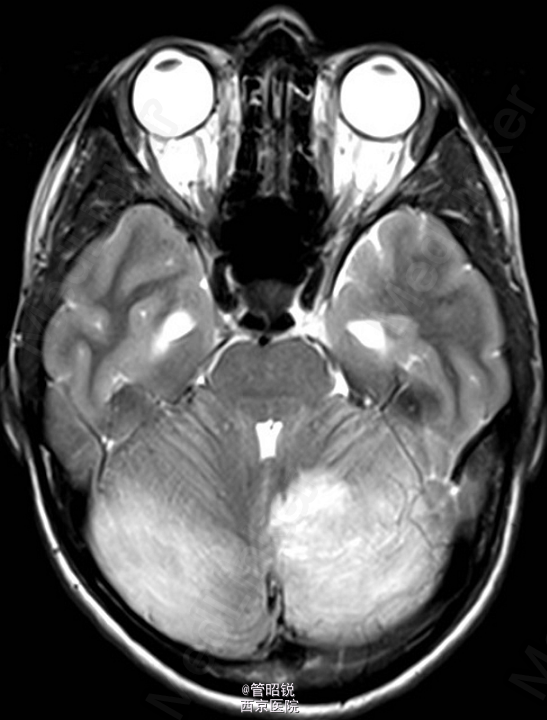

患者,男,29岁,头痛、颈痛2周 入院时CT正常,24小时后 T2WI (B) 和 T2W-FLAIR (C)显示高信号增强,脑水肿,沟回消失。CE-T1WI (D)显示脑膜线样增强。随后12小时的非增强CT显示小脑水肿压迫脑干,由于阻塞性脑积水使颞角膨大,需要紧急行颅后窝颅骨切除减压术。(影像资料比较典型。和大家分享下 AJNR-case of the week)

诊断:急性小脑炎 治疗上应早期应用激素治疗,水肿严重时应手术行颅骨减压。

急性小脑炎是以小脑功能损害为主的炎性综合症。发病前期一般有感染病史,多见于儿童。临床表现多样,主要有躯干和肢体的共济失调,发热,眼球运动异常,言语不清,头痛,恶心、呕吐和意识水平的下降。临床诊断主要依据其典型的影像学检查,临床表现和脑脊液检查结果。